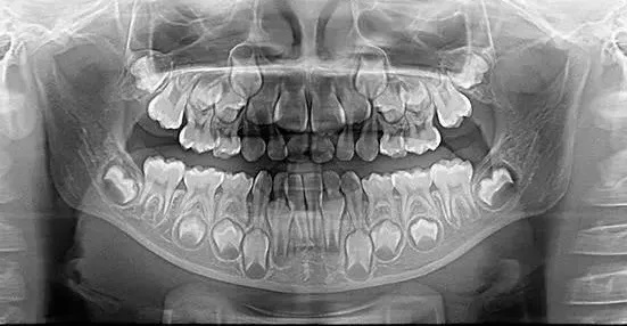

全景片

X光拍片为什么要等小朋友看牙为什么要拍片?_https://www.jmylbn.com_新闻资讯_第8张

以检查全口牙齿为目的,全景片可以观察到全口牙的形态、位置、颌骨等情况,比如乳牙下方是否有恒牙牙胚在发育、牙颌的畸形程度等等。全景片是儿童看牙最常用到的一种X线片。